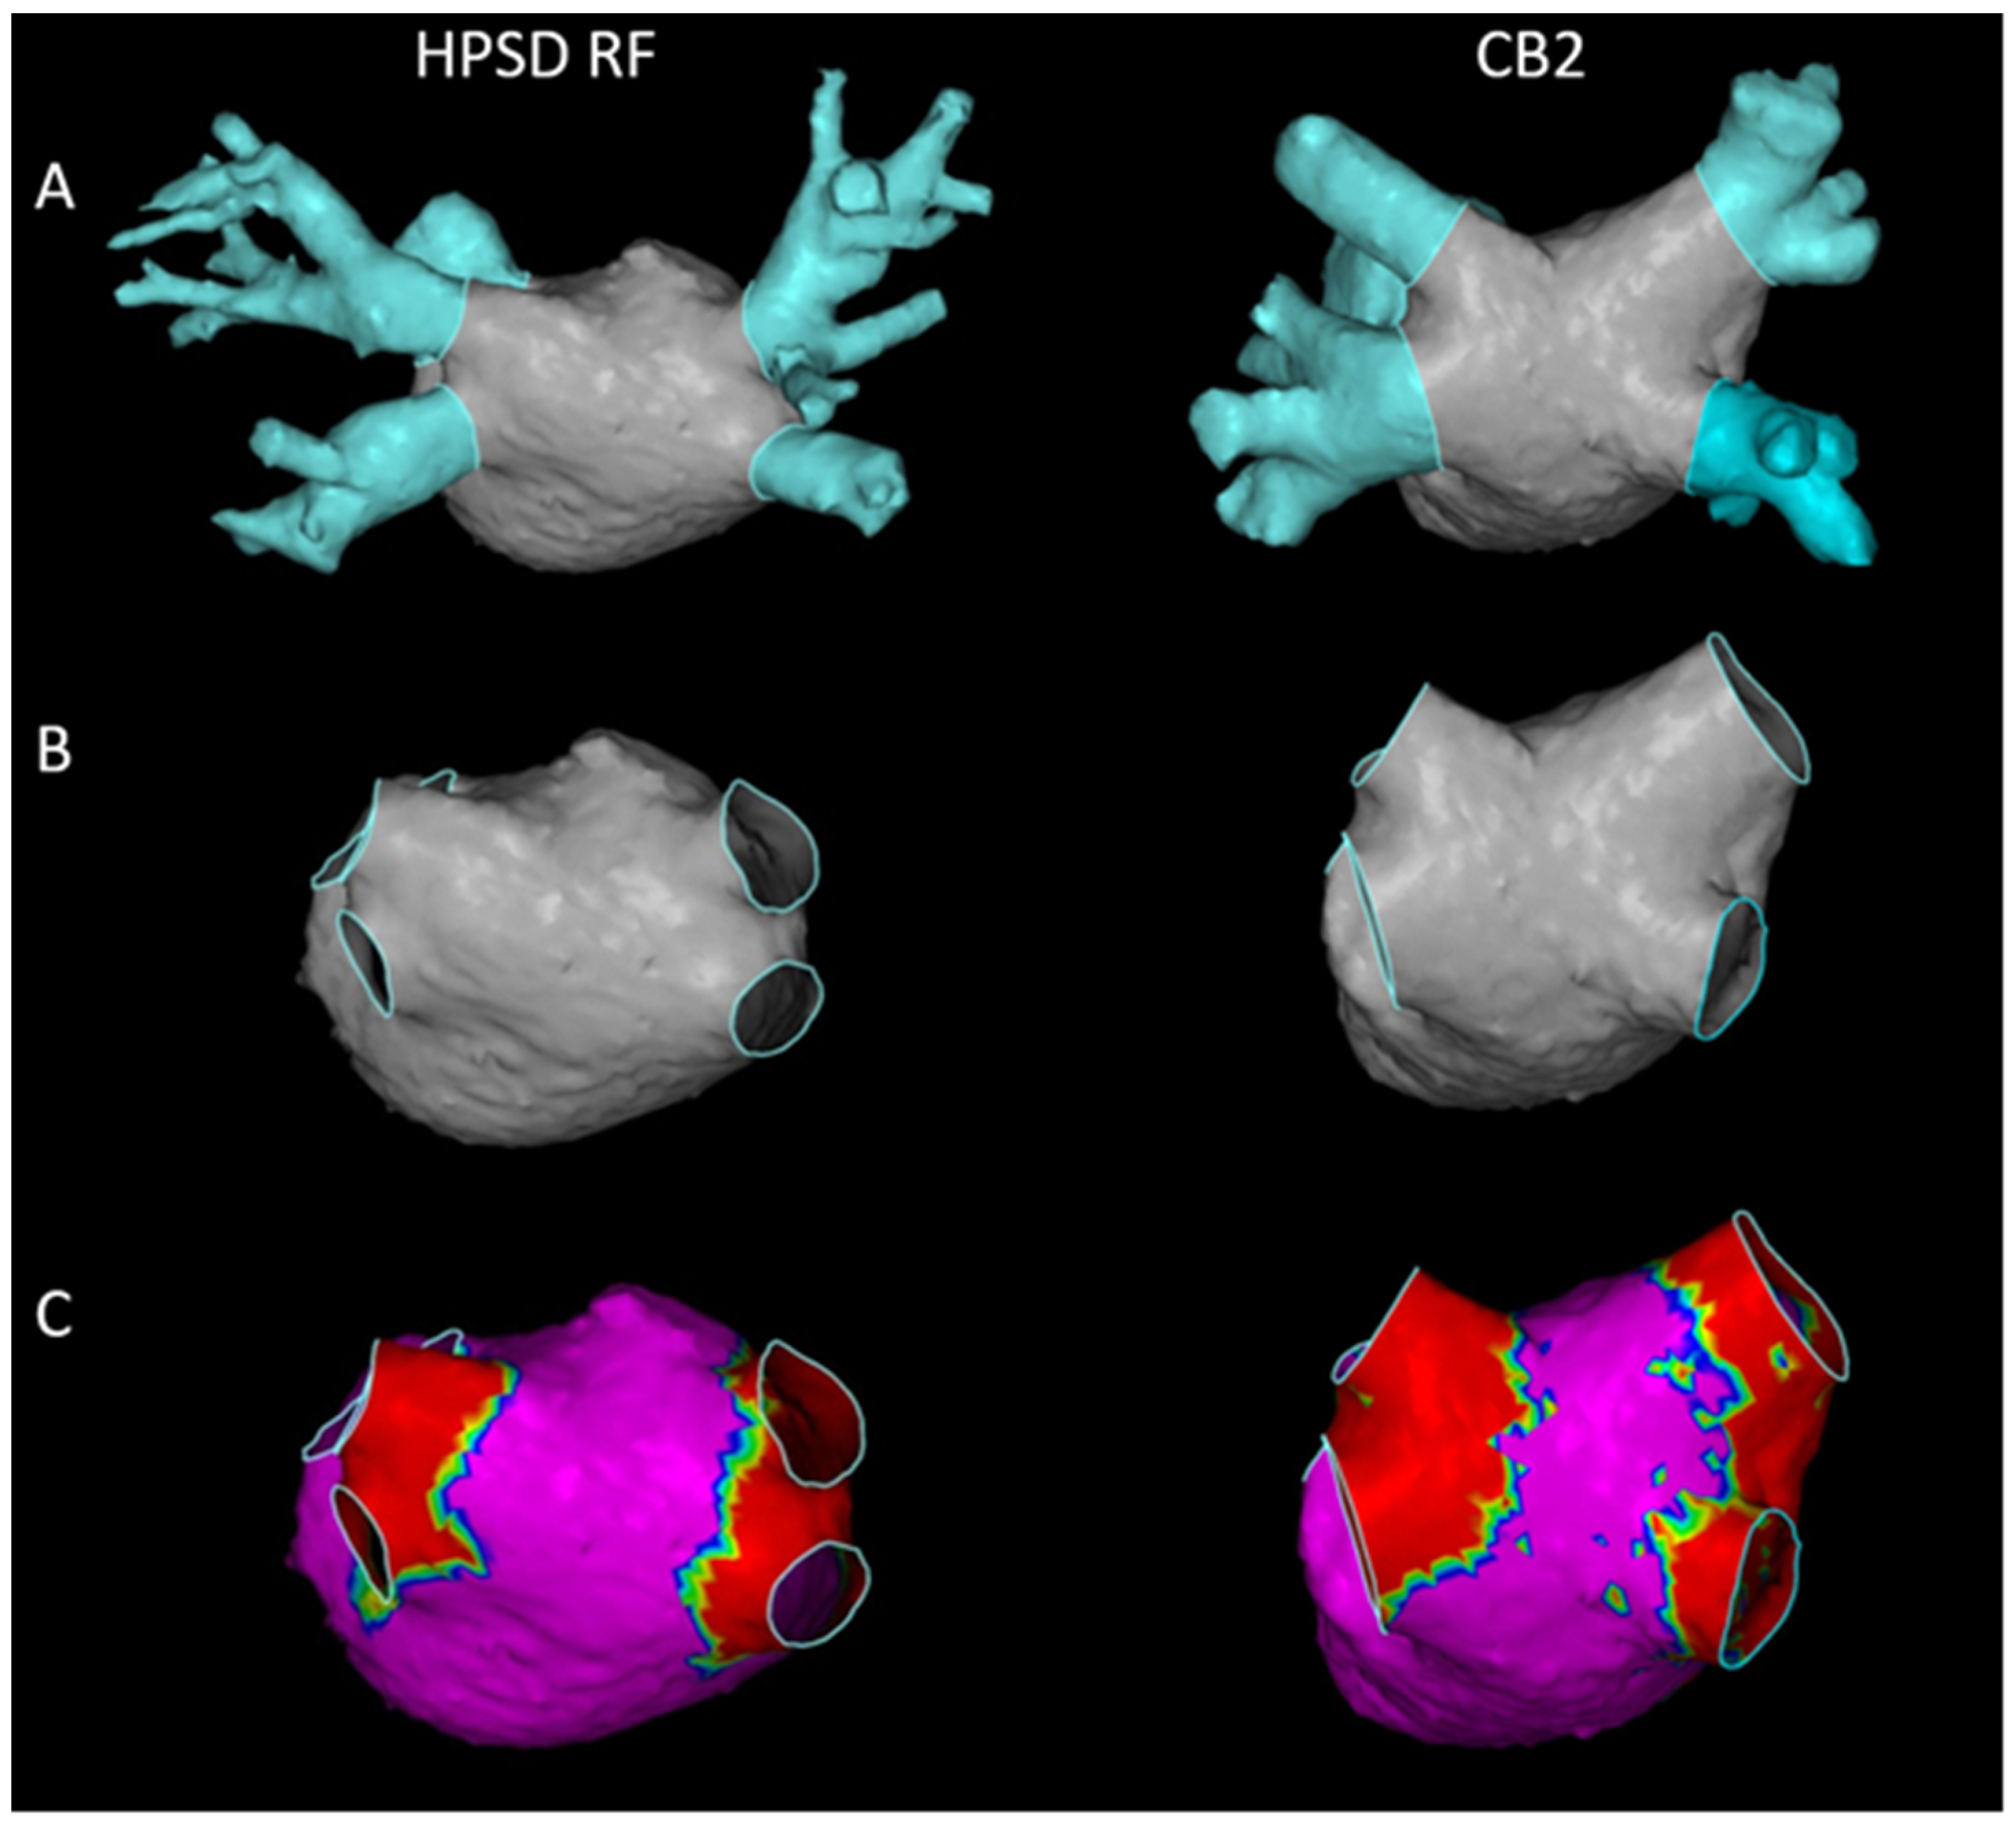

3.5. Comparison of Isolation Areas

4.4. Isolation Area after HPSD RF and CB2 Ablation

| LA Surface and LVA Measurements | |||

|---|---|---|---|

| HPSD RF (n = 21) | CB2 (n = 19) | p Value | |

| Number of points per map | 1748 ± 477.7 | 1660 ± 477.3 | 0.606 |

| Match statistics (mm) | 3.559 ± 0.951 | 3.706 ± 1.063 | 0.740 |

| Left atrial (LA) surface (cm2) | 100.1 ± 18.5 | 95.9 ± 18.1 | 0.472 |

| Normal voltage area (NVA) (cm2) | 92.1 ± 18.1 | 83.1 ± 19.4 | 0.170 |

| Low voltage area (LVA) (cm2) | 8.45 ± 6.60 | 12.80 ± 8.02 | 0.039 |

| LVA/LA surface (%) | 8.37 ± 6.42 | 13.58 ± 8.92 | 0.022 |